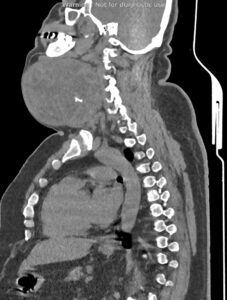

در سی تی اسکن اسپیرال از گردن ، ریه و مدیاستن با و بدون تزریق (مولتی دیدکتور 16 با مقاطع ظریف و بازسازی های ساژیتال و کرونال):

بیمار آقای 44 ساله با توده گردنی جهت بررسی بیشتر، مراجعه نمودند:

تصویر توده بزرگ به ابعاد 118x133mm در پلن آگزیال و دیامتر کرانیو کودال 126mm در سمت چپ گردن با نمای هتروژن و کلسیفیکاسیون Coarse مرکزی رویت می شود. به نظرمنشا توده ذکر شده از لوب چپ تیروئید می باشد. گسترش فوقانی توده تا سطح مهره دوم گردنی و زیر زاویه مندیبل و گسترش تحتانی آن تا ناحیه سوپراکلاویکولار بدون گسترش اینتراتوراسیک رویت می شود.

اثر فشاری توده ذکر شده به تراشه با انحراف آن به سمت مقابل رویت می شود.

اثر فشاری توده ذکر شده به ورید ژوگولارداخلی و CCA با جابه جایی خلفی و به SCM با جابه جایی خلفی لترال آن مشهود است.

مجموع یافته ها مطرح کننده توده تیروئید با اثرات ذکر شده می باشد.